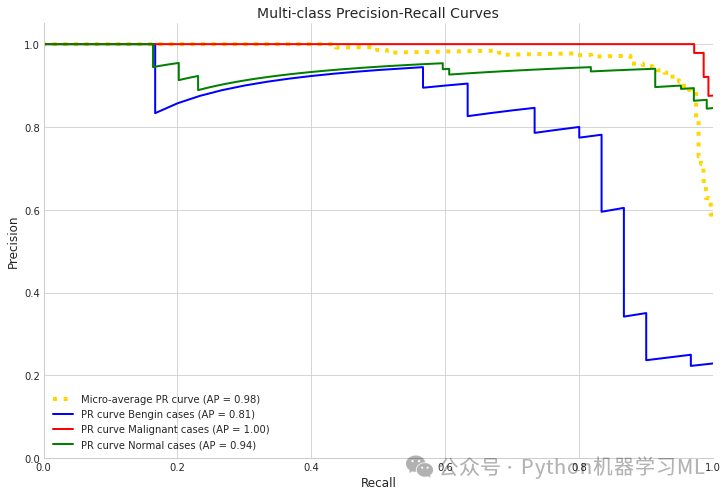

第五****阶段:精确度-召回率曲线

python# 5. Precision-Recall curves

from sklearn.metrics import precision_recall_curve, average_precision_score

# Use different variable names to avoid conflict

pr_precision = dict() # 创建字典存储精确度

pr_recall = dict() # 创建字典存储召回率

average_precision = dict() # 创建字典存储平均精确度

for i inrange(n_classes):

y_valid_bin = np.zeros((len(y_valid), n_classes)) # 创建全零矩阵用于一热编码

for j inrange(len(y_valid)):

y_valid_bin[j, y_valid[j]] = 1# 将真实标签转换为一热编码

pr_precision[i], pr_recall[i], _ = precision_recall_curve(y_valid_bin[:, i], y_pred_proba[:, i]) # 计算每个类别的PR曲线参数

average_precision[i] = average_precision_score(y_valid_bin[:, i], y_pred_proba[:, i]) # 计算每个类别的平均精确度

# Calculate micro-average precision-recall curve

pr_precision["micro"], pr_recall["micro"], _ = precision_recall_curve(y_valid_bin.ravel(), y_pred_proba.ravel()) # 计算micro-average的PR曲线

average_precision["micro"] = average_precision_score(y_valid_bin.ravel(), y_pred_proba.ravel()) # 计算micro-average的平均精确度

# Plot precision-recall curves

plt.figure(figsize=(12, 8)) # 创建图形

plt.plot(pr_recall["micro"], pr_precision["micro"],

label=f'Micro-average PR curve (AP = {average_precision["micro"]:.2f})',

color='gold', linestyle=':', linewidth=4) # 绘制micro-average的PR曲线

colors = cycle(['blue', 'red', 'green']) # 定义颜色循环

for i, color inzip(range(n_classes), colors):

plt.plot(pr_recall[i], pr_precision[i], color=color, lw=2,

label=f'PR curve {categories[i]} (AP = {average_precision[i]:.2f})') # 绘制每个类别的PR曲线

plt.xlim([0.0, 1.0]) # 设置x轴范围

plt.ylim([0.0, 1.05]) # 设置y轴范围

plt.xlabel('Recall') # 设置x轴标签

plt.ylabel('Precision') # 设置y轴标签

plt.title('Multi-class Precision-Recall Curves') # 设置标题

plt.legend(loc="lower left") # 添加图例

plt.grid(True) # 添加网格

plt.show() # 显示图形

第六阶段:模型性能摘要报告

python# 6. Generate model performance summary report

print("\n=== Model Performance Summary ===")

print(f"Micro-average AUC: {roc_auc['micro']:.4f}") # 打印微平均AUC

print(f"Class average AUC: {np.mean([roc_auc[i] for i in range(n_classes)]):.4f}") # 打印类别平均AUC

print(f"Micro-average Precision-Recall Area: {average_precision['micro']:.4f}") # 打印微平均PR曲线下面积

# Print detailed metrics for each class

for i in range(n_classes):

print(f"\nClass: {categories[i]}")

print(f"AUC: {roc_auc[i]:.4f}") # 打印每个类别的AUC

print(f"Precision: {class_precision[i]:.4f}") # 打印每个类别的精确度

print(f"Recall: {class_recall[i]:.4f}") # 打印每个类别的召回率

print(f"F1-Score: {class_f1[i]:.4f}") # 打印每个类别的F1分数

=== Model Performance Summary ===Micro-average AUC: 0.9873Class average AUC: 0.9739Micro-average Precision-Recall Area: 0.9762

Class: Bengin casesAUC: 0.9471Precision: 0.9375Recall: 0.5000F1-Score: 0.6522

Class: Malignant casesAUC: 0.9980Precision: 0.9928Recall: 0.9716F1-Score: 0.9821

Class: Normal casesAUC: 0.9766Precision: 0.8512Recall: 0.9904F1-Score: 0.9156